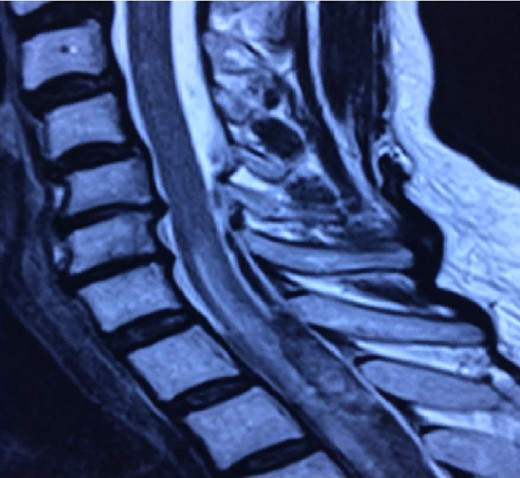

Patient presented sudden onset with dorsal pain followed immediately by bilateral lower extremity paresis that progressed to complete paraplegia with bowel and bladder dysfunction over 15 min. The patient was taken to a local hospital where an MRI was performed that demonstrated a SSDH extending from T4 to T7 with some intramedullary enhancement noted (Figs 1 and 2). Loss of sensory level from T10 up to ~T8 level. She denied upper extremity complaints.

Magnetic resonance remains the imaging modality of choice for the diagnosis of spinal hematomas [4, 7]. SSDHs are less probable to occur in the upper thoracic region rather than the lower thoracic region. Unequivocally, hematomas are described as subdural if there is no displacement of the dura mater. Spinal hematomas are classified into phases according to the relation between symptom onset and MRI realization.

When the subdural hematoma is discovered during the hyperacute phase, such as with the patient described in the case report, the blood collection is visualized as isointense and hyperintense in T1 and T2 signals, respectively. The intensity will normally vary according to the phase in which the MRI has been performed [4, 7, 8]. Once the presence and location of the subdural hemorrhage are determined it is fundamental to decide the optimal treatment for the patient unhesitantly.